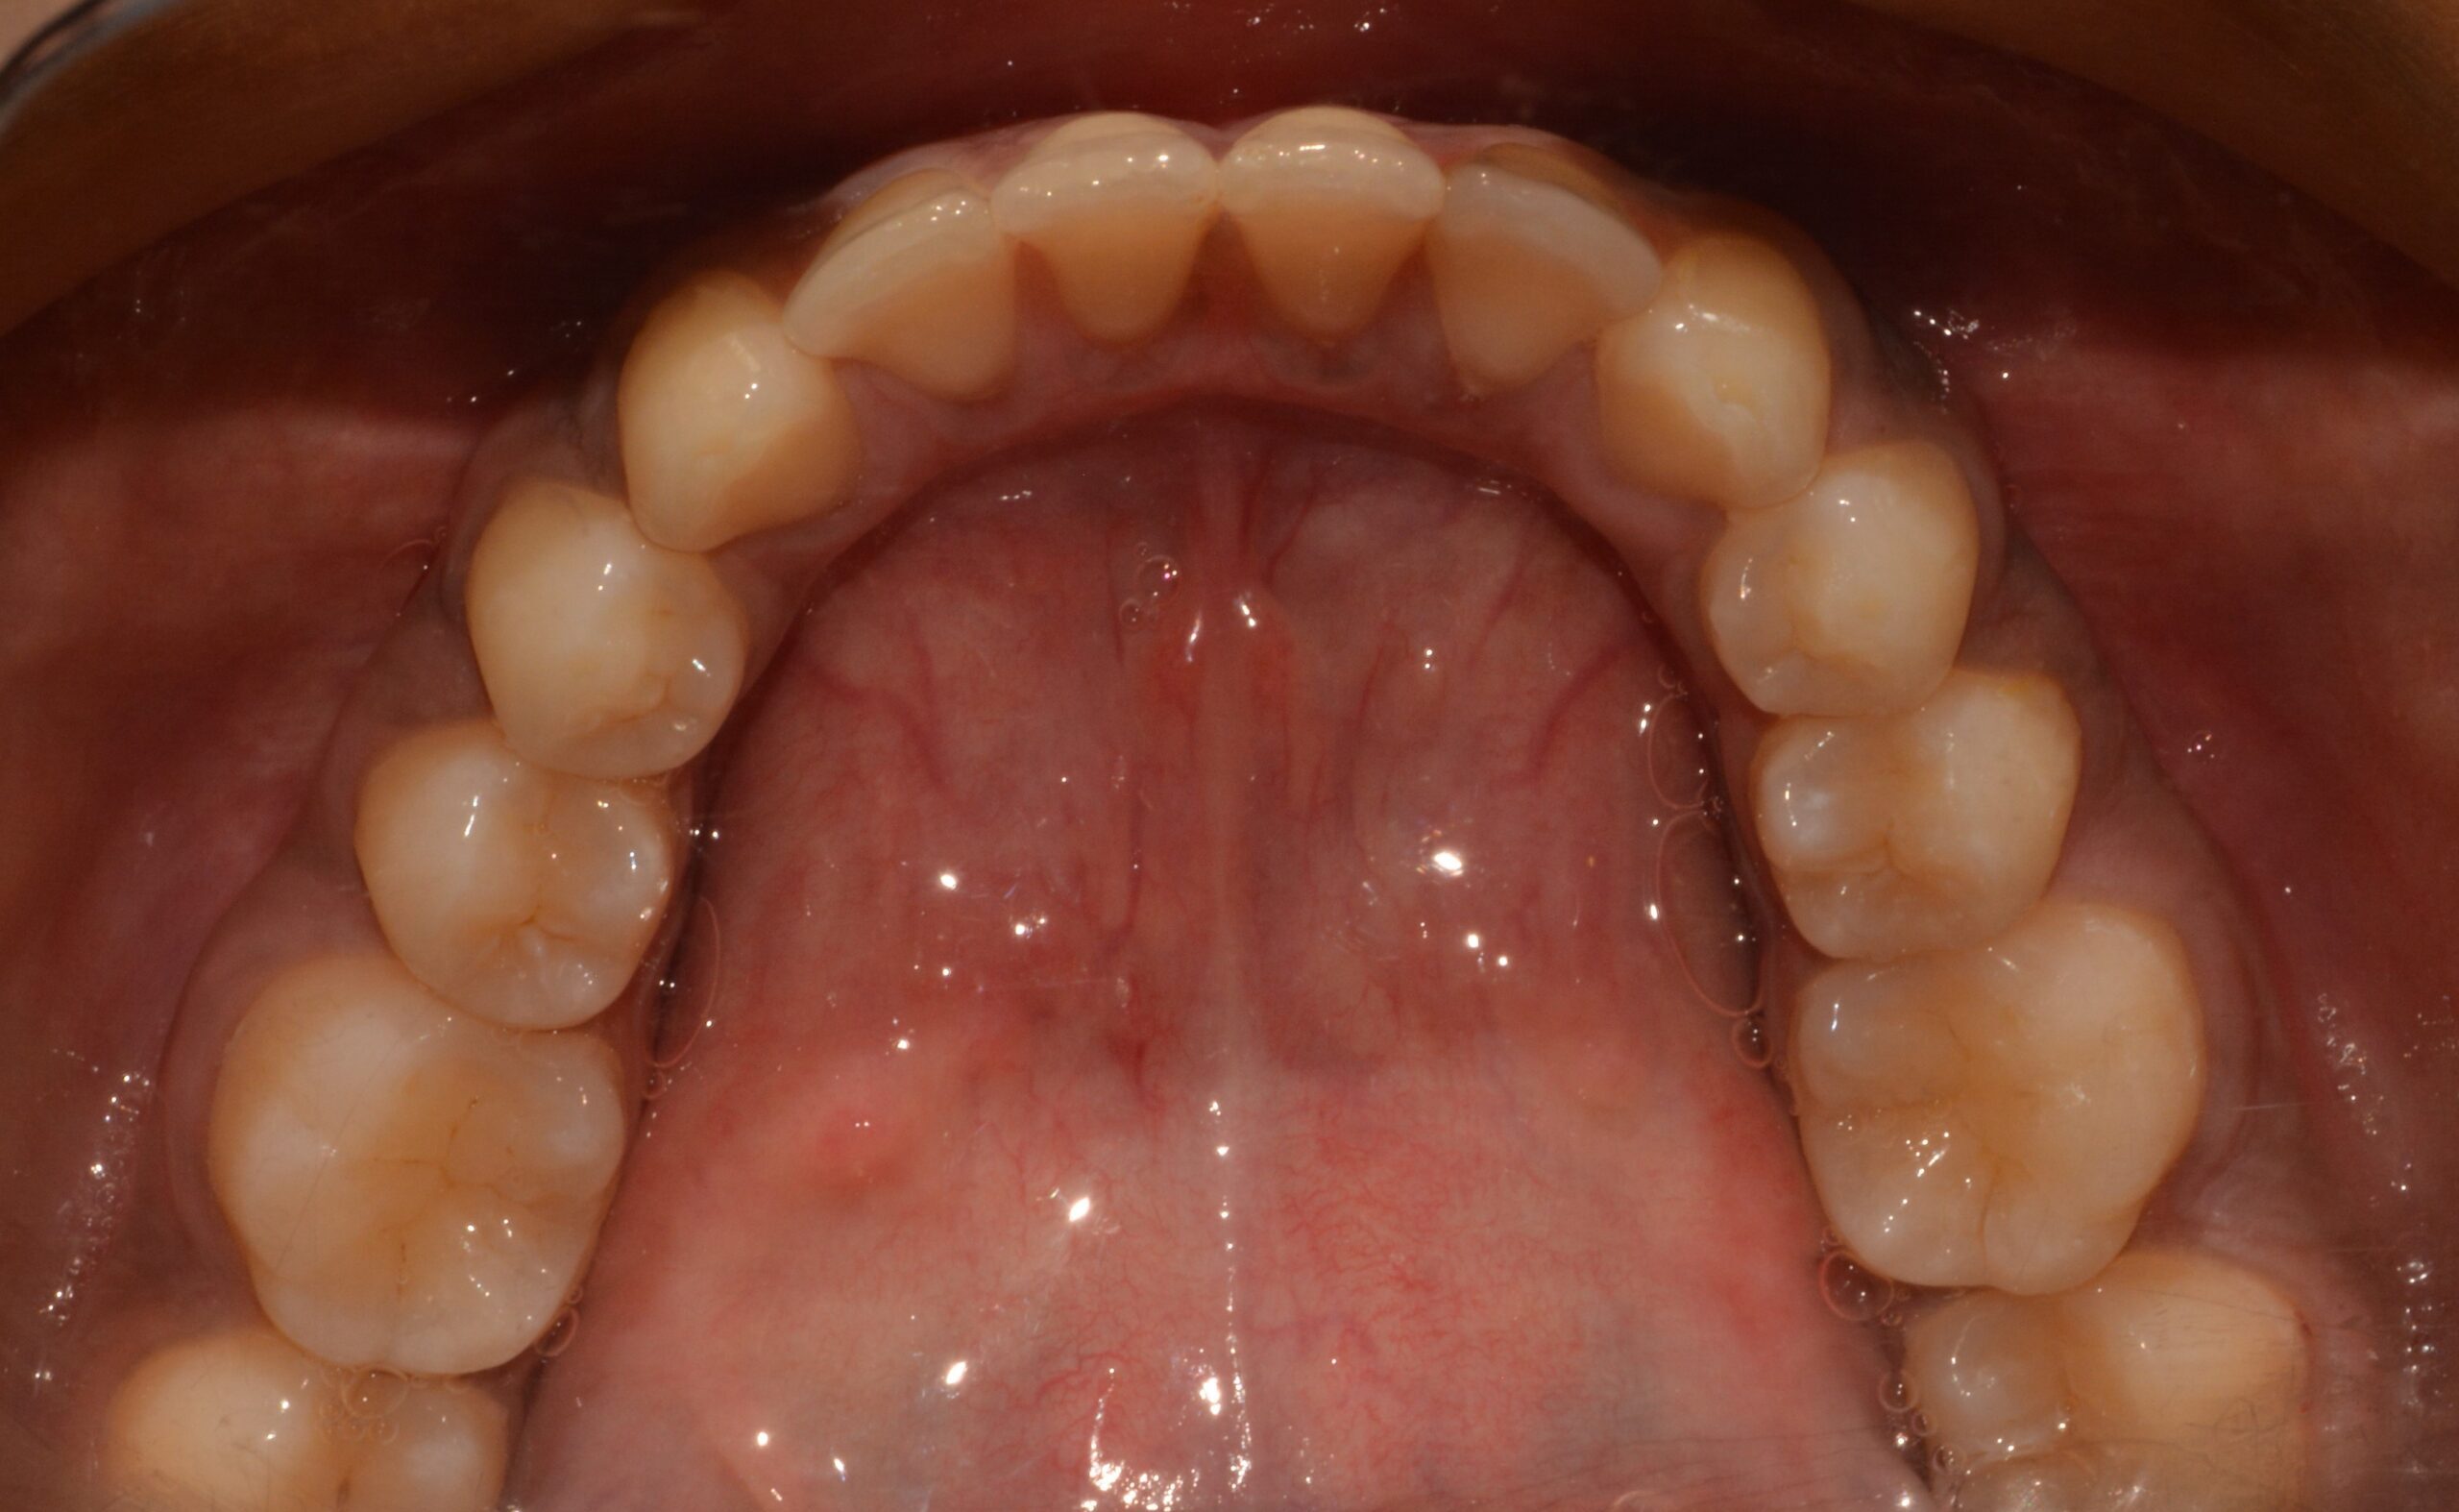

The patient was treated with aligner therapy using Invisalign aligners, which applied light forces to close the gaps. This treatment also helped the loose lower front teeth become stable over time, preventing the need for tooth removal and future implants.

The total treatment duration was between 18 to 20 months.

Before

After